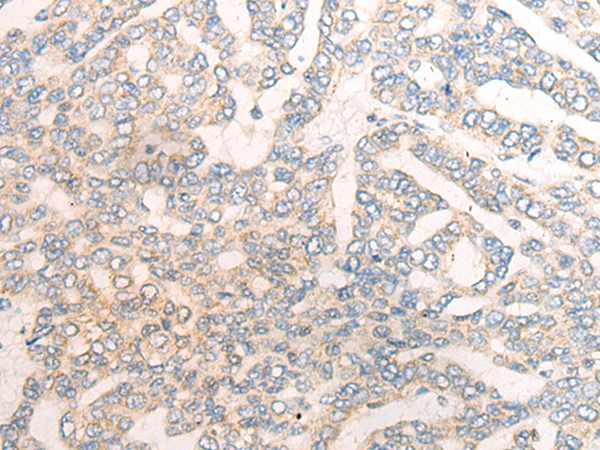

分类: 科研抗体货号: P07697别名:应用: WB,IHC反应种属: Human, Mouse